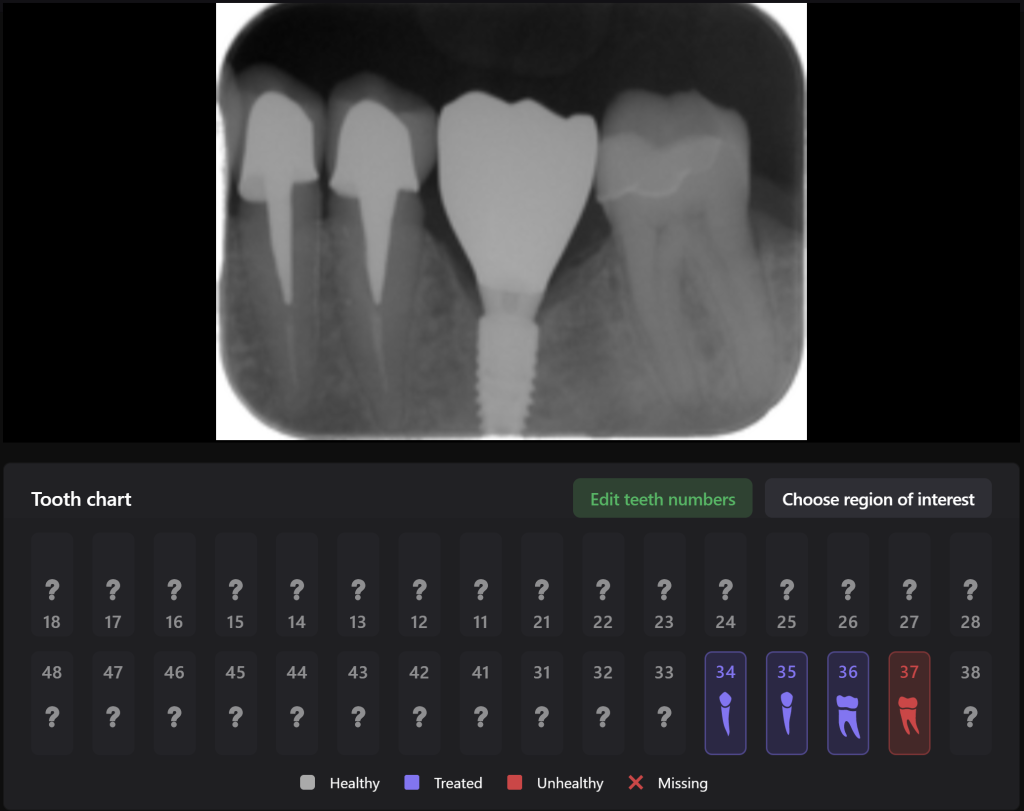

An intraoral radiograph was uploaded into the Diagnocat FMX module, this demonstrates the most favorable prosthetic position for the implant